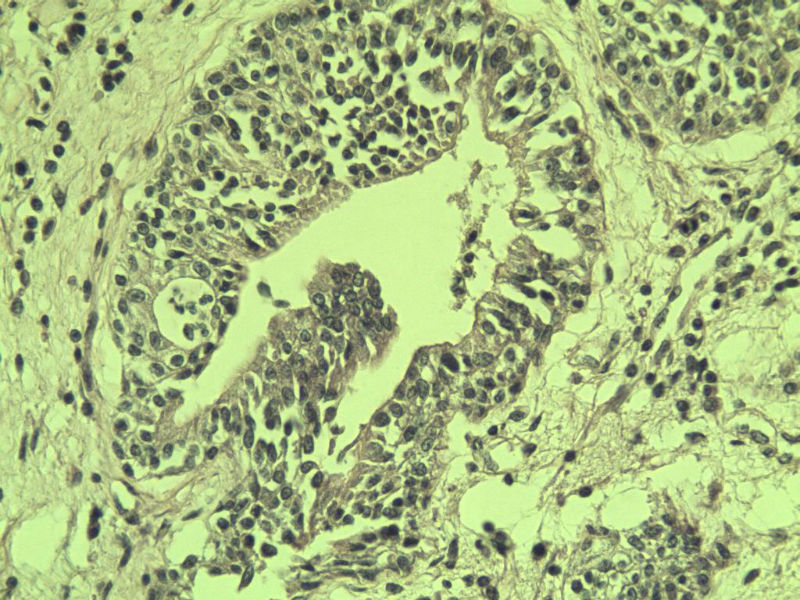

男 75岁 因排尿困难半年行前列腺切除术,体积 4 × 3 × 2.5 cm3,切面灰白,实性,质韧。请各位老师看看 有问题没? 谢谢了!

高级别上皮内瘤变,建议免疫组化:P63、34BE12、P504S

前列腺增生症伴鳞化

良性前列腺增生

良性前列腺增生伴尿路上皮化生

前列腺增生伴尿路上皮鳞化及Brown巢形成,未见恶性。